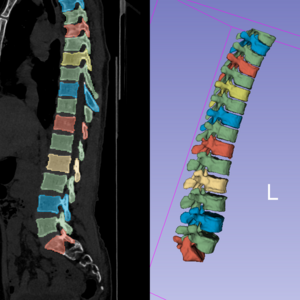

Musculoskeletal health in Indigenous populations

RenderedCT

Studying an Indigenous forager-horticulturalist population to provides unique insights into skeletal aging in the absence of many modern risk factors.